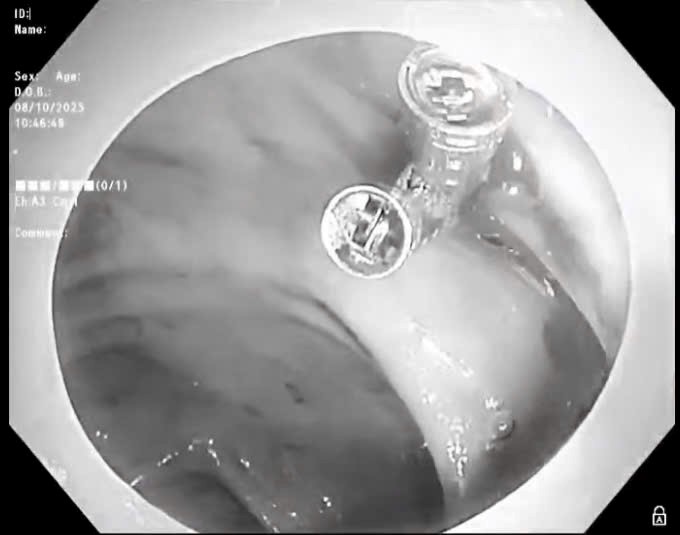

BVĐK Sóc Sơn cấp cứu thành công ca bệnh sốc giảm thể tích do xuất huyết tiêu hóa

Friday 2025-10-17 05:02Vừa qua, Bệnh viện đa khoa (BVĐK) Sóc Sơn đã tiếp nhận bệnh nhân Đỗ Văn P (69 tuổi) ở Sóc Sơn, được người nhà đưa đến bệnh viện cấp cứu. Các bác sĩ xử trí kịp thời ca bệnh sốc...